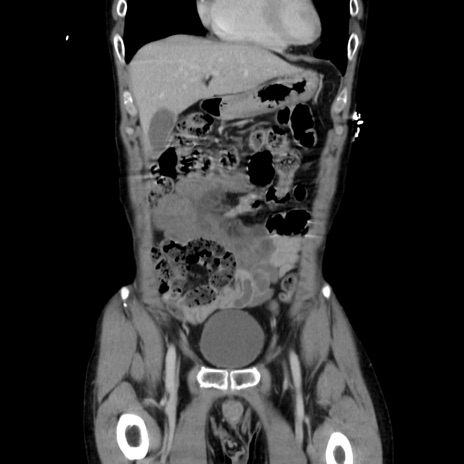

症例37(冠状断像)

【症例】40歳代 男性

【主訴】腹痛

【現病歴】4時間ほど前に電車に乗車中に臍部上より腹痛出現。徐々に増悪し起立困難となり、救急外来受診。生ものは数日食べていない。今朝お雑煮を食べた。

【身体所見】BT 36.8℃、BP 117/84mmHg、HR 91/min、SpO2 97%、苦悶様、腹部:臍上部広範囲圧痛あり、反跳痛±

【データ】WBC 8100、CRP 0.03